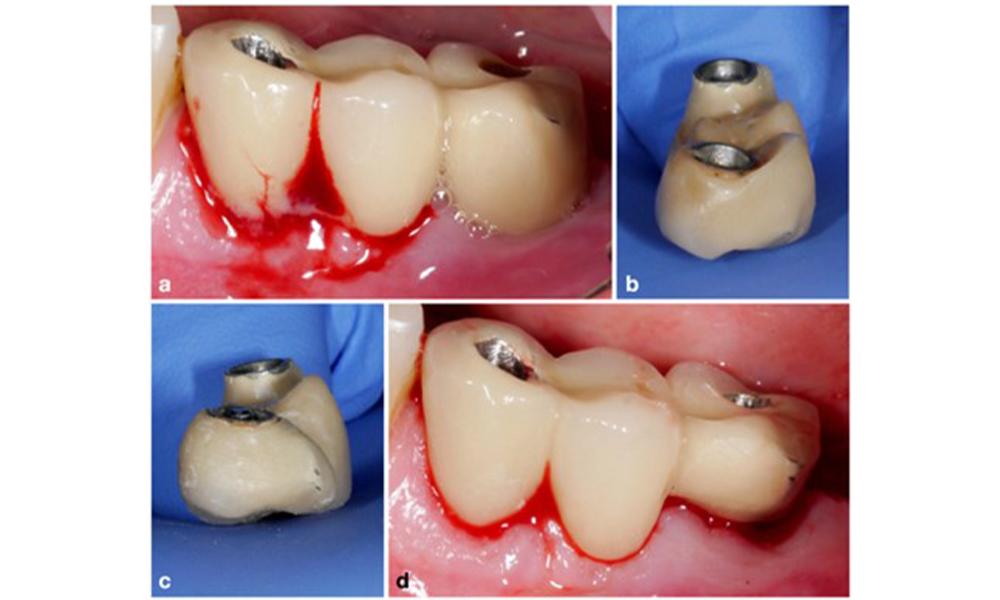

Изборът на средство зависи от клиничните обстоятелства, като например разликата между зъбен камък и мека плака. По този начин, в случаите със зъбен камък първо трябва да се използват титаниеви или пластмасови кюрети или специални накрайници за ултразвукови скалери, последвани от използването на устройство за въздушно полиране (фигура 7). В случаите само с натрупване на мека плака може да е достатъчно само въздушно полиране. Устройствата за въздушно полиране са лесни за ползвателя и пациента и са поне толкова ефективни, колкото стандартните инструменти (Schwarz et al. 2015a).

Случай на пациент с периимплантатен мукозит, лоша орална хигиена и натрупване на зъбен камък (a). В този случай е препоръчително комбинирането на различни устройства. Например за отстраняване на зъбния камък са необходими специални накрайници за ултразвукови скалери (b), докато останалия мек биофилм може да се отстрани с устройство за въздушно полиране (c–d).

Фигура 7. Случай на пациент с периимплантатен мукозит, лоша орална хигиена и натрупване на зъбен камък (a). В този случай е препоръчително комбинирането на различни устройства. Например за отстраняване на зъбния камък са необходими специални накрайници за ултразвукови скалери (b), докато останалия мек биофилм може да се отстрани с устройство за въздушно полиране (c–d).